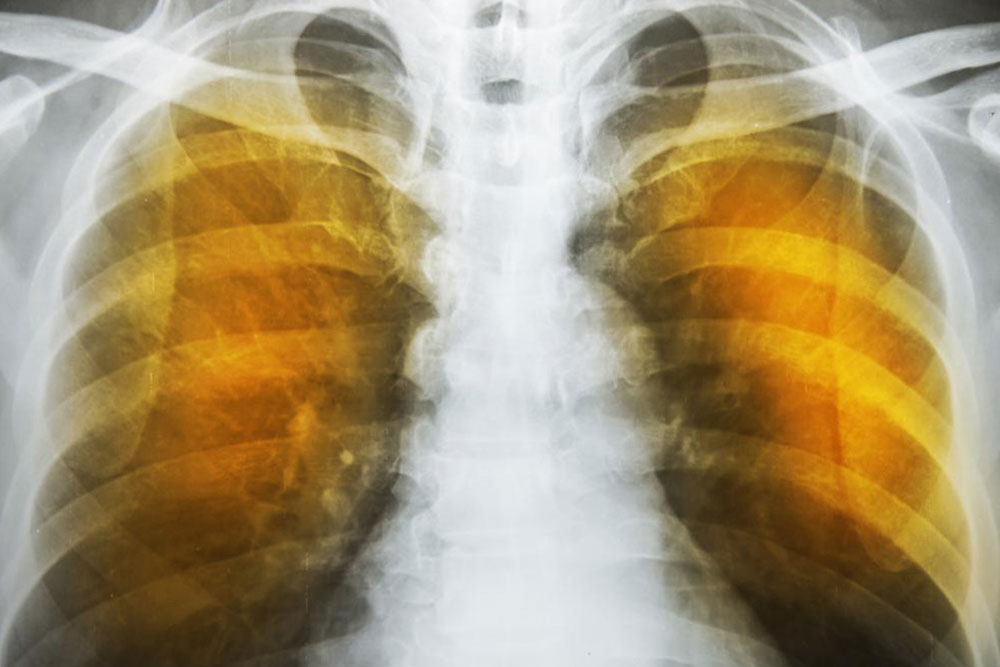

What is emphysema and what are its complications?

Emphysema is an oppressive respiratory disorder which results from the disintegration of the alveoli, i.e., the tissues where the interchange of gas with blood takes place. Destruction in any large scale will reduce the gas transfer area and the process of gas transfer itself, leading to oxygen starvation or hypoxia. When conventional treatment with bronchodilators, corticosteroids etc. have ceased to give relief, one has to resort to a method known as Long Term Oxygen Therapy or LTOT.

Chronic hypoxia sets in a chain of reactions. The body tries to compensate the hypoxia by increasing cardiac output and increasing the concentration of red corpuscles by producing more of them in the bone marrow. Both are effective to an extent but the oxygen demand, as the disease progresses, cannot be fully met. This leads to the development of a condition called cor pulmonale’. This gradually leads to pulmonary hypertension, increasing the load on the right side of the heart.

The right cardiac chambers dilate to accommodate and gradually leads to hypertrophy. The end of these chain reactions is right-sided heart failure and death.

Another complication is the alveoli becoming weaker, and then starting to break. When this assumes larger scale, vacant spaces are formed called bullae. This reduces the gas transfer area as well as the capacity of the lung to expand. These are often have to be surgically removed to allow more space for the lung to expand. In the ultimate case, lung transplant becomes the only choice. Another scenario is a large-scale disintegration of alveoli that can cause pneumothorax, which is a condition in which the chest cavity is filled with air and the lungs collapse. This is a very serious condition if not fatal.